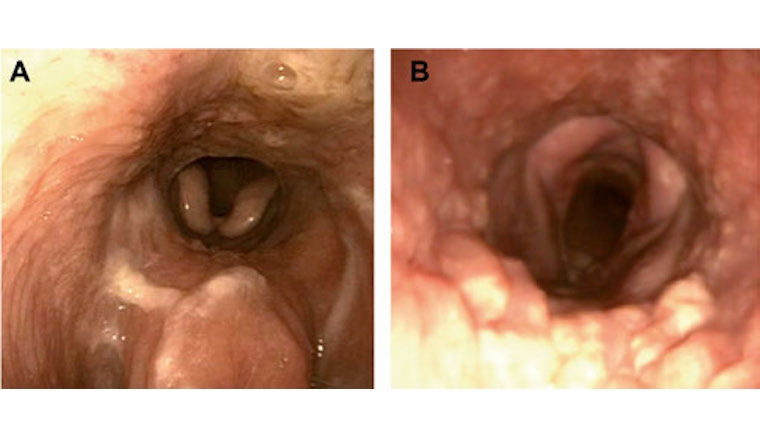

D'autres résultats prometteurs ont été présentés au Bovine Respiratory Disease Symposium, en 2019. Les chercheurs ont évalué par endoscopie l'inflammation de l'appareil respiratoire supérieur de veaux vaccinés contre les virus de la rhinotrachéite infectieuse et de la diarrhée virale bovine, puis infectés par ces mêmes agents. L'inflammation était nettement moins forte chez les animaux ayant reçu une injection d'oligo-éléments (cf. photo 1). Ces résultats n'ont pas encore été publiés et demandent à être validés.